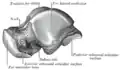

Left talus, medial surface -

Left talus, lateral surface